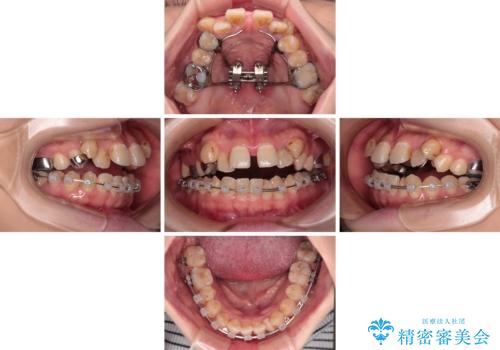

- 上下の歯が非接触であり、八重歯やむし歯を気にして来院された患者様です。

下顎骨の左右偏位はあるものの、上顎骨幅が相対的に狭い状態であったので、奥歯の咬み合わせが非常に乱れていました。

急速拡大装置により上顎骨幅を側方に拡大し、それを利用して八重歯を歯列に納めることにしました。